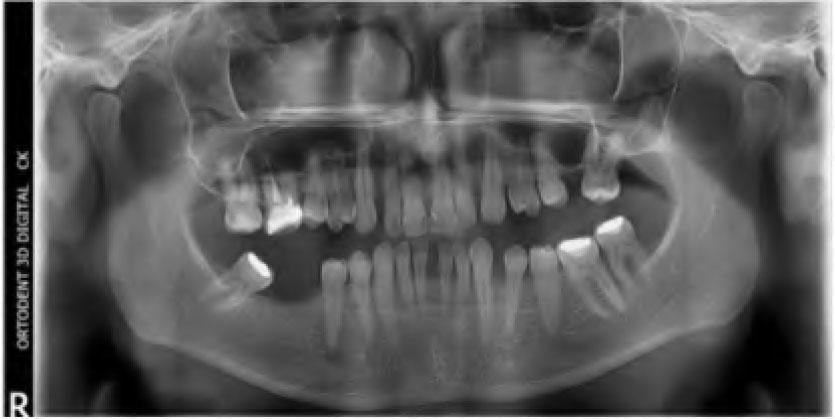

Intraoral and radiograph examination verified that 26 and 46 were missing and the endodontic treatment of 16 was no adequately performed. Caries lesions were found on the mesial surfaces of 11, 21 and 12. There was no pocket depth of over 2 mm or mobility around any of the remaining teeth. Panoramic radiograph confirmed that all the maxillary and mandibular teeth had favorable crown/root ratio of 2:3 (Figure 2). The patient’s oral hygiene was good.

Panoramic radiograph before treatment